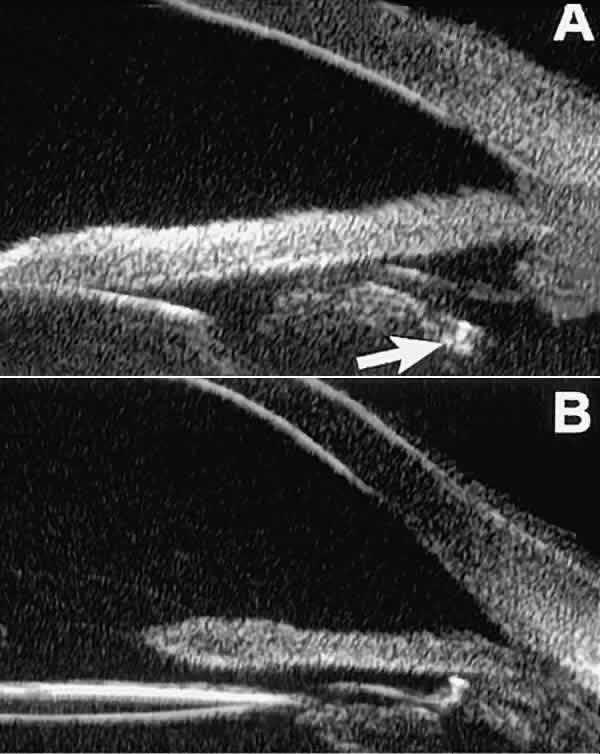

Fig. 18 . Localization of posterior chamber IOL haptics by UBM. A. Haptic in capsular bag (arrow). B. Haptic (bright object just behind peripheral iris) in iridociliary sulcus.

Ultrasound biomicroscopy appears to be helpful postoperatively in determining the extent of postoperative complications of cataract surgery such as serous choroidal detachment (see Fig. 13A), iridocapsular adhesion (Fig. 19A), postoperative hyphema (see Fig. 19B), stripping of Descemet's membrane (see Fig. 19C), and wound gaping (see Fig. 19D).

Fig. 19. Complications of cataract surgery revealed by UBM. A. Capsular adhesion to midzone of iris. B. Postoperative hyphema. Clot appears denser than aqueous with suspended blood cells. C. Stripping of Descemet's membrane. D. Wound gape.